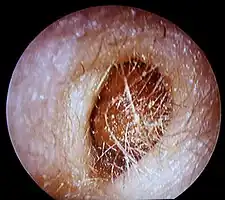

Bouchon de cérumen

De manière générale, le cérumen est naturellement éliminé de l’oreille ou est emporté à l’extérieur par de l’eau, par exemple, lors de la douche. Cependant, il se peut qu’une accumulation excessive de cérumen forme un bouchon partiel ou complet. Des causes possibles de cet accumulation excessive sont[7] :

Ces symptômes ne sont cependant pas spécifiques du bouchon de cérumen et peuvent être dus à d'autres causes. Il est recommandé de consulter un médecin ou un professionnel de la santé auditive qui pourra vérifier à l'aide d'un otoscope la présence ou non d'un bouchon ou encore d’un corps étranger[9].